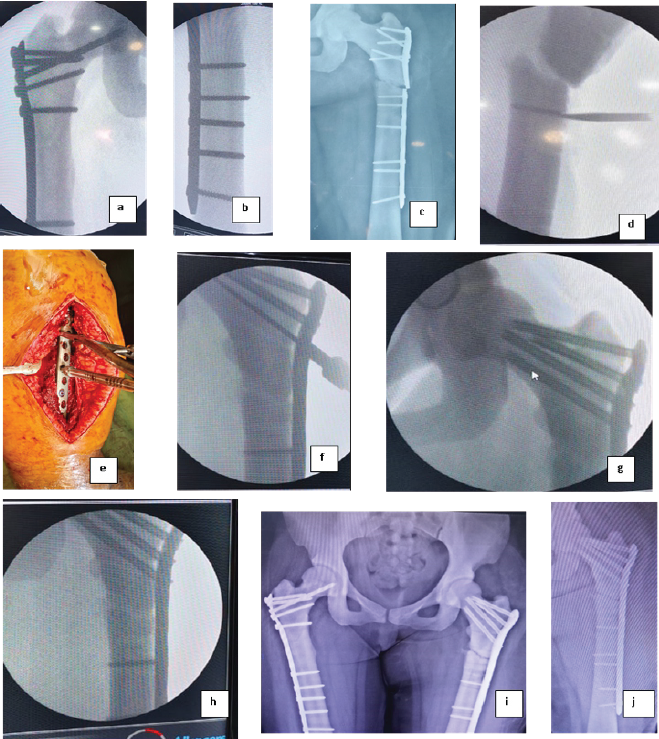

A 29y/F presented to our side with complaints of pain and swelling over left thigh following trivial trauma. She had a history of fracture of shaft femur left side which was managed by operative intervention six months ago. She also had history of surgical fixation of fracture shaft femur right side 2 years back. Her vitals were within normal range. On local examination Slight swelling of the left thigh. Local tenderness and percussion pain on the left thigh. the right hip, knee, ankle, and toes range of motions were normal. Good bilateral peripheral pulses and perfusion. Bilateral hip, pelvic, and thigh xray confirmed subtrochanteric fractures with broken plate and screws in situ left side, and right sided united fracture subtrochanteric fracture with distal femur LCP (Locking Compression Plate) in-situ.

The left complete fracture was treated with removal of plate and screws and open reduction and internal fixation (ORIF) using a proximal femoral locking plate as there was no visible medullary canal on radiographs. The patient received spinal anesthesia and was positioned in lateral decubitus [Fig. 2]. A standard lateral incision was made, and screws were removed carefully with the help of a hexagonal screw driver, during the process, on screw head and shaft junction was broken, and that screw was removed with the help of a hollow mill, after that, the fracture was reduced, with temporary fixation achieved using bone-holding forceps and K-wires. Fluoroscopic guidance was used to confirm reduction. [Fig. 2]

Figure 2: Case II. (a and b) Old united subtrochanteric fracture right side fixed with plate, (c) fracture subtrochanteric femur left side with broken proximal humerus interlocking plate osteosynthesis system plate in situ, (d) intraoperative fluorescent imaging showing while removing implant screw head breakage was encountered, (e) Intraoperative positioning (lateral decubitus) and plate placement, (f-h) Intraoperative fluorescent imaging showing proximal femoral anatomical locking plate fixation, (i) Post-operative picture – right sided united fracture subtrochanteric femur with distal femur locking plate in situ and fixed fracture subtrochanteric femur with proximal femoral anatomical locking plate in situ showing good reduction and alignment, (j) Post-operative picture of plate fixation.

For definitive fixation, a long proximal femur anatomical locking plate was selected. This plate comes with cannulated screws in the neck for that the guidewire is inserted with sleeve guidance. In one instance, after guide wire insertion cannulated drill bit was inserted during this process, the guide wire was broken; hence, it was left in situ. [Fig. 2] Due to the increased bone density characteristic of osteopetrosis, several modifications to standard surgical techniques were necessary. Same method of drilling was used as mentioned in case I. Here also we employed a tap for better insertion due to the significantly increased cortical density. The duration of surgery was 3 hours, and blood loss was approximately 300 mL. The surgery was completed successfully without any other complications.

Post-operative course

Post-operative X-rays confirmed accurate placement of the internal fixation on the left femur, with good apposition and alignment of the fracture fragments. The patient’s recovery was uneventful, and she was discharged with instructions for follow-up and rehabilitation. The patient was allowed weight-bearing after 3 months.